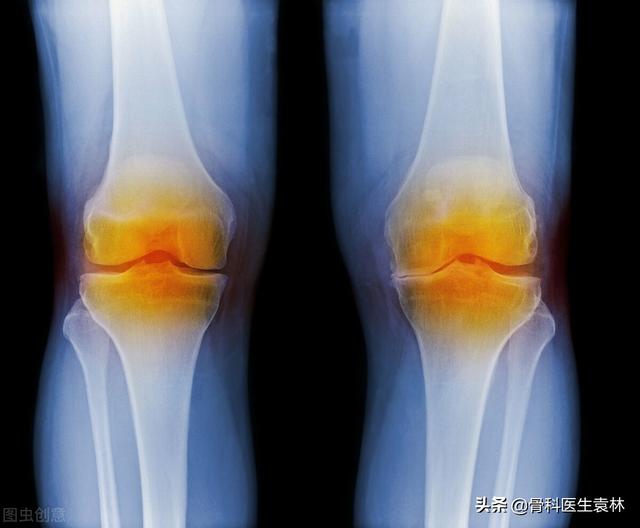

关节炎,是骨科的常见炎性疾病,多发生在人体关节及其周围组织。关节炎有很多种类型,关节炎常见,我国的患者也有很多。生活中很多人都有膝盖关节炎的症状,只是有些患者症状不是很严重也就忽视了该疾病的存在。

虽然很多人都知道关节炎这种疾病,但是有些患者对该疾病了解的并不完善,所以也就忽视了该疾病的存在。今天我就带大家了解一下关节炎早期症状有哪些?关节炎该怎么治疗?

关节炎早期的症状有哪些?